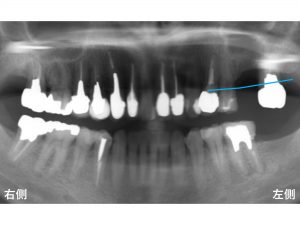

以下が初診時です。

上顎左側奥から2番目が欠損しています。

骨が吸収しているのです。

以下の青線が骨吸収する前の元々の骨の位置です。